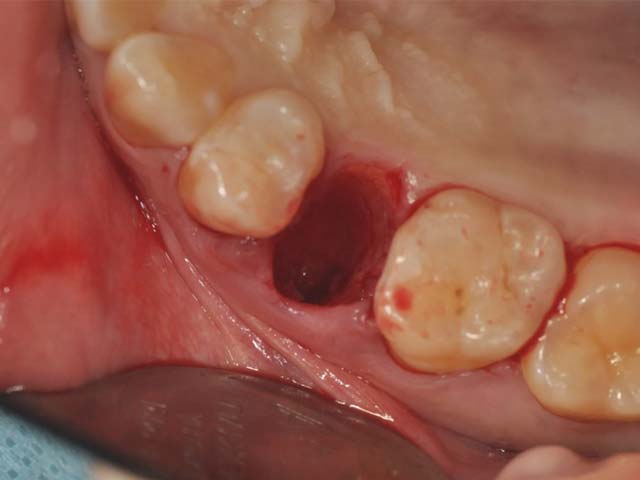

齒槽骨保存術+植牙 首頁 案例分享 人工植牙 齒槽骨保存術+植牙 STEP1拔除掉無法使用的斷裂牙根 STEP2齒槽骨保存術—使用骨粉填補拔牙傷口 術前 V.S 術後 植牙第一階段—植入牙根 植牙第二階段—製作正式假牙